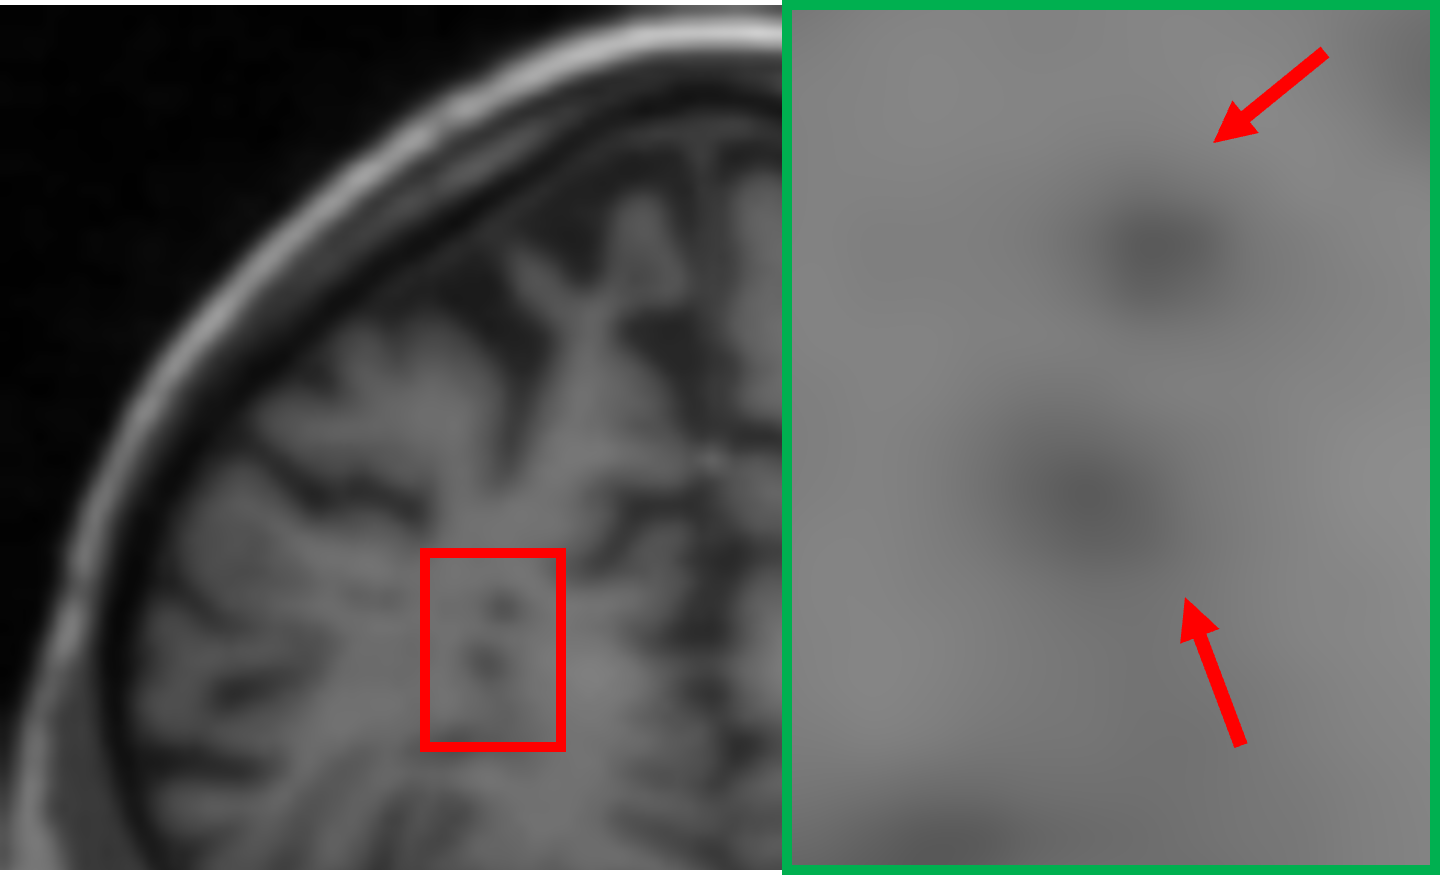

IV-C Visualization of the expert specialization

To further elucidate the functional specialization of each expert within the proposed MoE framework, we visualize the difference maps between each expert’s output and the ground truth 7T MRI. These maps are computed by taking the pixel-wise absolute difference between the expert output and the ground truth 7T MRI, highlighting the residual discrepancies and reconstruction focus of each expert. In the visualizations, lighter areas reflect lower reconstruction errors, suggesting better alignment with the ground truth. As shown in Fig. IV, each column represents the output of a particular expert, visualized through its corresponding absolute difference map with respect to the 7T reference. The final output is computed via a weighted combination of expert outputs. The visualized difference maps underscore the distinct specialization of each expert. Specifically, Expert 1 exhibits minimal residuals in homogeneous white matter regions, preserving large-scale anatomical continuity. Its low-frequency focus is evident in the smooth residual patterns and coherent structural boundaries. Expert 2 demonstrates heightened sensitivity to cortical regions and sulcal boundaries, with pronounced residual suppression around edges and high-frequency details. Expert 3 shows enhanced reconstruction accuracy at tissue interfaces and transitional zones. The residuals are particularly reduced in regions of sharp contrast changes. These observations confirm that each expert effectively targets specific anatomical and textural characteristics, guided by their unique architectural and loss function design. The gating mechanism further facilitates optimal integration by adaptively weighting expert contributions according to the local image context, thus ensuring a globally coherent and anatomically faithful 7T-like reconstruction.

TABLE IV: Visualization of the expert specialization

E1subscript𝐸1E_{1}italic_E start_POSTSUBSCRIPT 1 end_POSTSUBSCRIPT E2subscript𝐸2E_{2}italic_E start_POSTSUBSCRIPT 2 end_POSTSUBSCRIPT E3subscript𝐸3E_{3}italic_E start_POSTSUBSCRIPT 3 end_POSTSUBSCRIPT Final

[Uncaptioned image] [Uncaptioned image] [Uncaptioned image] [Uncaptioned image]

𝒢1=0.21subscript𝒢10.21\mathcal{G}_{1}=0.21caligraphic_G start_POSTSUBSCRIPT 1 end_POSTSUBSCRIPT = 0.21 𝒢2=0.48subscript𝒢20.48\mathcal{G}_{2}=0.48caligraphic_G start_POSTSUBSCRIPT 2 end_POSTSUBSCRIPT = 0.48 𝒢3=0.31subscript𝒢30.31\mathcal{G}_{3}=0.31caligraphic_G start_POSTSUBSCRIPT 3 end_POSTSUBSCRIPT = 0.31 Weighted

• *

The expert-specific weights (𝒢1subscript𝒢1\mathcal{G}_{1}caligraphic_G start_POSTSUBSCRIPT 1 end_POSTSUBSCRIPT, 𝒢2subscript𝒢2\mathcal{G}_{2}caligraphic_G start_POSTSUBSCRIPT 2 end_POSTSUBSCRIPT, 𝒢3subscript𝒢3\mathcal{G}_{3}caligraphic_G start_POSTSUBSCRIPT 3 end_POSTSUBSCRIPT) for this particular slice are dynamically computed by the gating network 𝒢𝒢\mathcal{G}caligraphic_G.